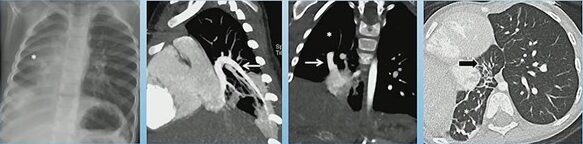

Scimitar Syndrome with Horseshoe Lung: Hypoplastic right lung, PAPVR to RA, horseshoe lung, R lung bronchiectasis

One of the most notable associations is horseshoe lung, seen in approximately 80% of cases. Horseshoe lung consists of a parenchymal isthmus connecting both lungs across the midline, usually posterior to the heart. When present, it further reinforces the diagnosis and alerts the radiologist to search for additional congenital anomalies.